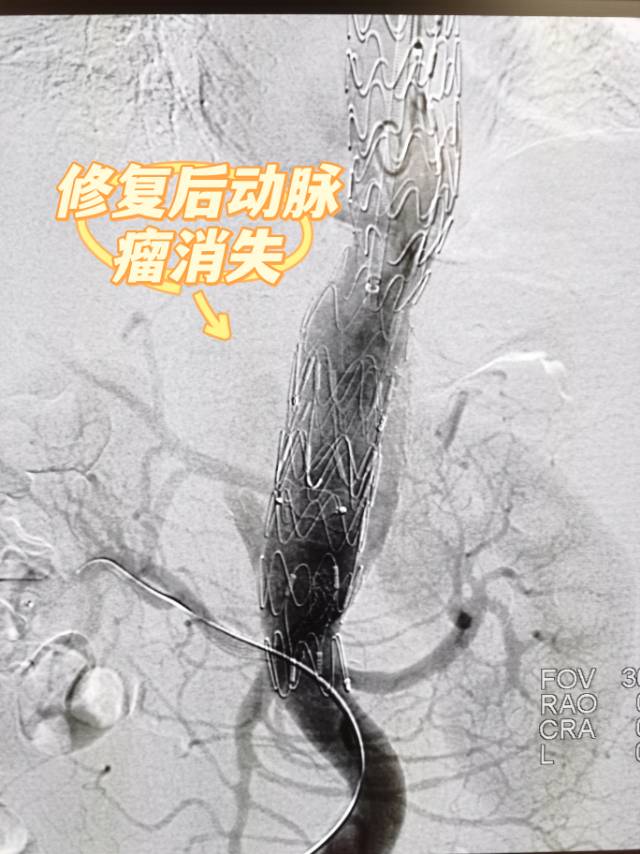

李娭毑入住了马王堆院区介入血管外科三病区(老年介入血管外科)。完善术前检查后,介入血管外科学科主任王庆教授组织了充分的术前讨论,仔细分析了病情及可能风险并制定了手术方案及相关预案。经过周密的术前准备,3月28日,在常务副院长向华教授的指导下,由王庆教授、颜鹏教授、欧阳尚副主任医师、李志军副主任医师、钱潇博医师共同主刀,成功为李娭毑实行了胸腹主动脉瘤介入手术治疗。术中通过对主体支架实行三开窗,采用多分支技术,在成功保留了肠系膜上动脉、双肾动脉的基础上,完整的隔绝了动脉瘤,达到了防止动脉瘤破裂的预期效果。李娭毑恢复顺利,麻醉苏醒后即可进食,2天后下床活动。术后4天复查CTA显示动脉瘤隔绝满意,各内脏动脉分支通畅,康复出院。